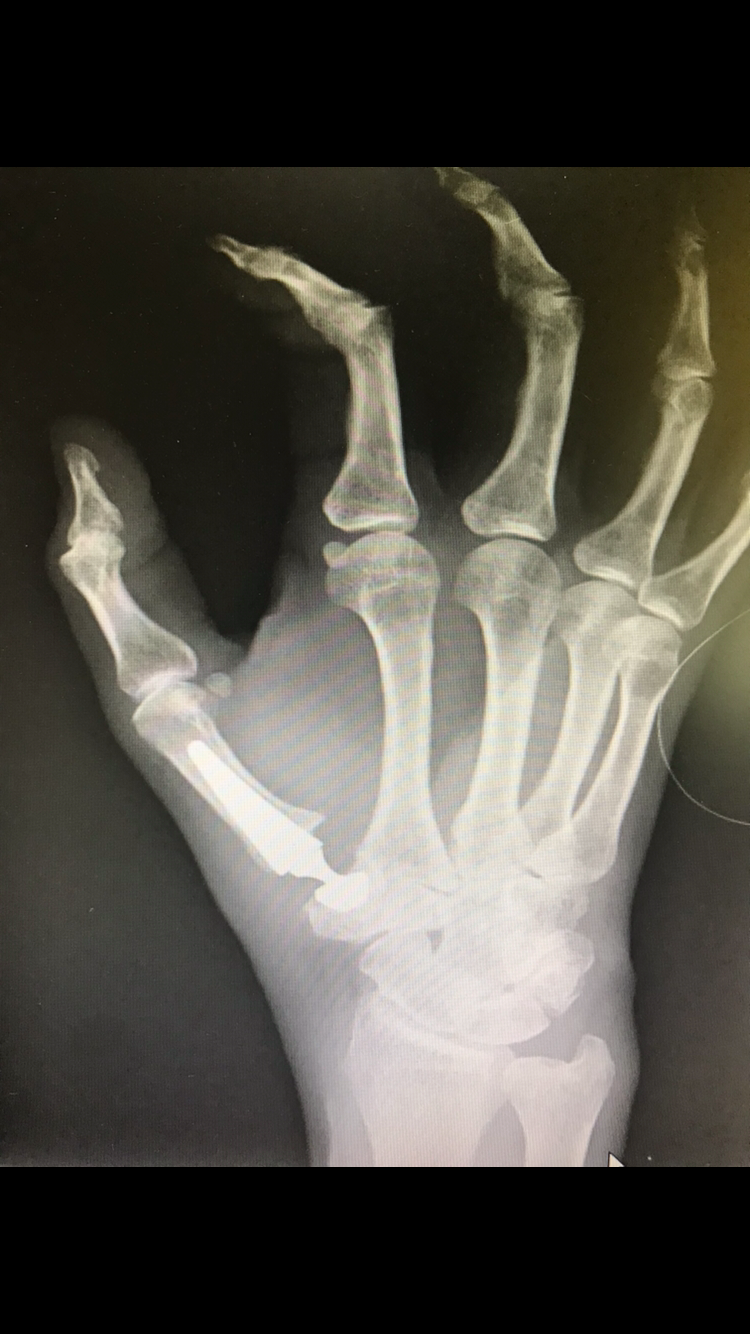

- Case 1 (Thumb arthroplasty)